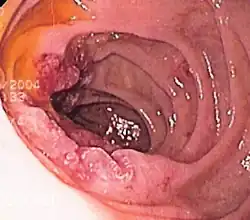

![]() Endoscopic still of esophageal ulcers seen after banding of esophageal varices, at time of esophagogastroduodenoscopy | |